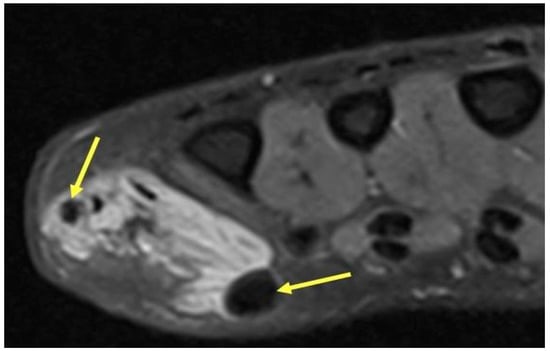

2.5. Glomus Tumors

2.5.1. Clinical Features

2.5.2. Imaging Appearance